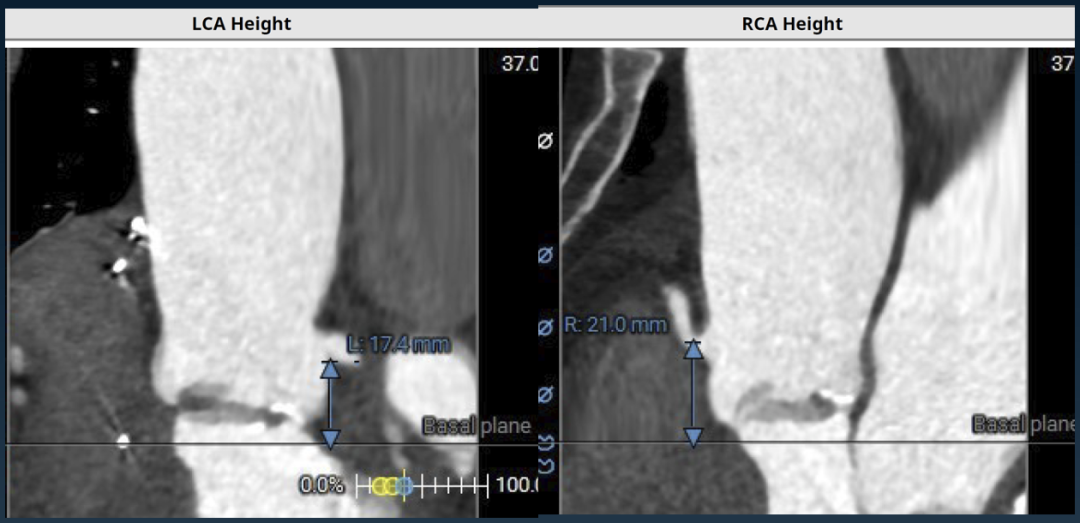

瓣环根部CTA

瓣环周长81mm,平均径25.8mm。SOV周长37.7*33.5*31.5mm

左冠高度:17.4mm,右冠高度:21.0mm

升主动脉最宽处44.9mm

HU850钙化积分:140mm²,轻度钙化